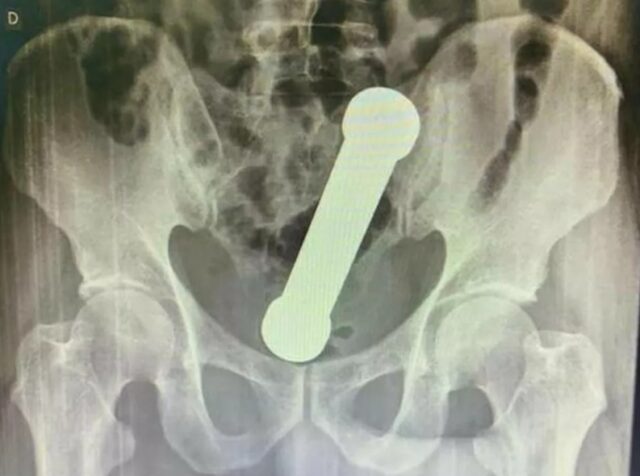

Foto: Reprodução/International Journal of Surgery Case Reports.

A partir do resultado do exame de radiografia, a equipe médica identificou um halter, utilizado em exercícios físicos, próximo ao reto do paciente. O homem então foi encaminhado ao centro cirúrgico e o objeto foi retirado de forma manual.

O halter retirado do homem era metálico, com cerca de 20 centímetros e 2 quilos. Segundo o estudo, a taxa de sucesso para extrações como a relatada no estudo, que são raras, é de 60% a 75%.